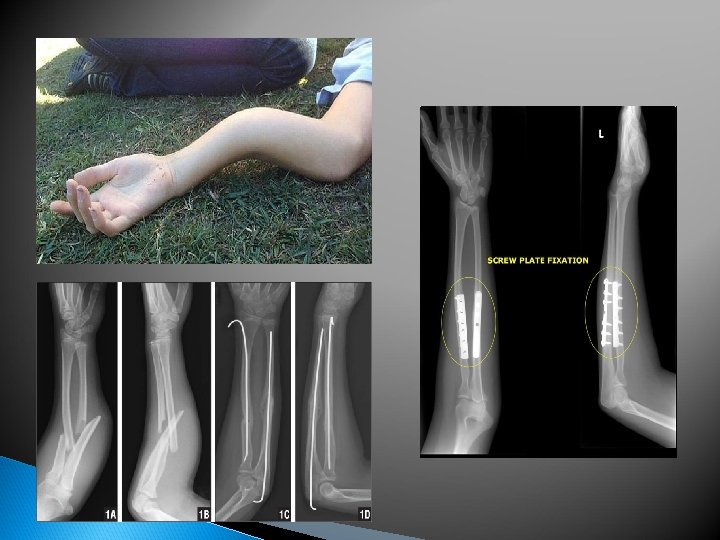

Forearm Fracture Cause: typically caused by a Signs & Symptoms: Pain, Care: Splint & immediately blow or falling on an outstretched hand swelling, deformity, ‘false joint’. There is a danger of soft tissue damage if the fractured bones move significantly refer for x-ray & physician consult. Ice. Typically casted for 6 -8 weeks, surgery may be required if the deformity is significant. Take Tylenol for pain, NOT Ibuprofen can delay fracture healing by hindering the inflammatory response phase

Forearm Fracture

Colles’ Fracture Cause: fall on outstretched hand forces the wrist into hyperextension. The most common forearm fracture. Distal Radius Fracture. Signs & Symptoms: visible deformity, pain, swelling, quick accumulation of blood. Median nerve damage is possible if the radius shifts forward enough Care: Splint & immediately refer for x-ray & physician consult. Ice. Typically casted for 4 -8 weeks. Fracture deformity is usually reduced under anesthesia.